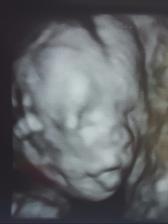

Gratuluji, je to veliký zázrak!!🙂 Z ničeho je malý tvoříček!! 🙂 už se těšíme na druhé,l ale ješte si poškáme, termín máme 01.01.2017